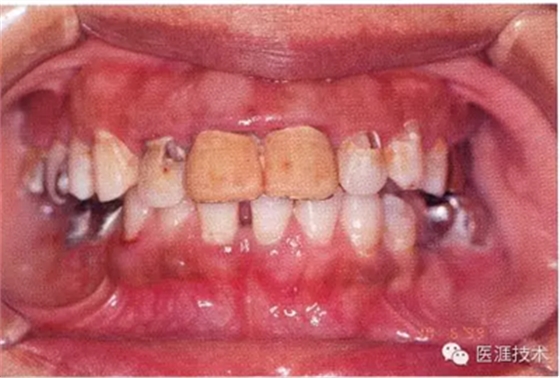

55歲牙周炎男性的臨床照片

55歲男性抽煙患者(1天20支、抽煙35年)。菌斑控制得不好。通過(guò)牙周探診,全頜有4~9mm的牙周袋,有1~3度的根分叉部病變。通過(guò)X光片觀察,上頜前牙中度牙槽骨吸收,其他地方有中度牙槽骨吸收。受吸煙影響,牙齦纖維性肥厚,呈紅黑色。牙齦幾乎沒(méi)有浮腫和發(fā)紅,所以這個(gè)病例是從外觀上無(wú)法預(yù)測(cè)病癥嚴(yán)重程度的病例。